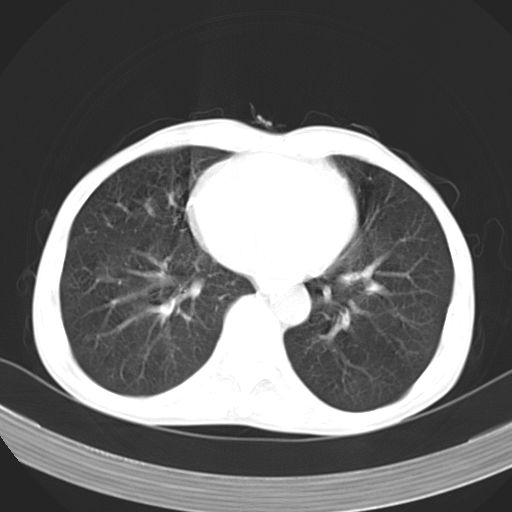

以下是引用苯小孩在2007-5-24 12:47:00的发言:[br]右侧肺门处不均匀密度软组织块影,远端肺组织见斑片模糊影,纵隔内淋巴结明显肿大,边界不清.<纵隔窗第12层面支气管内似见软组织结节>[br]考虑:1、右侧中央性肺癌并阻塞性肺炎并纵隔淋巴结转移可能性大.建议强化或纤支镜进一步检查.[br]2、隆突下淋巴结肿大/食道病变?请做鉴别检查.

以下是引用jw-830在2007-5-24 15:24:00的发言:[br][br] [br] 考虑右肺中央型肺癌并阻塞性炎症,右肺门及纵隔淋巴结转移。 [br] [br][br]